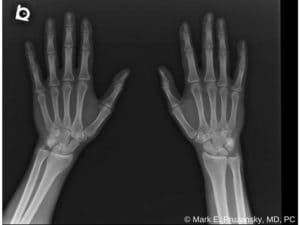

X-rays can show if a bone is broken and whether there is displacement (a gap between broken bones). Sometimes, a broken scaphoid does not show up on an x-ray right away. If this is the case, your doctor may put your wrist in a splint for a week or two. A new x-ray will be taken to see if the fracture will become visible. The splint should be worn during this waiting period, and heavy lifting should be avoided.